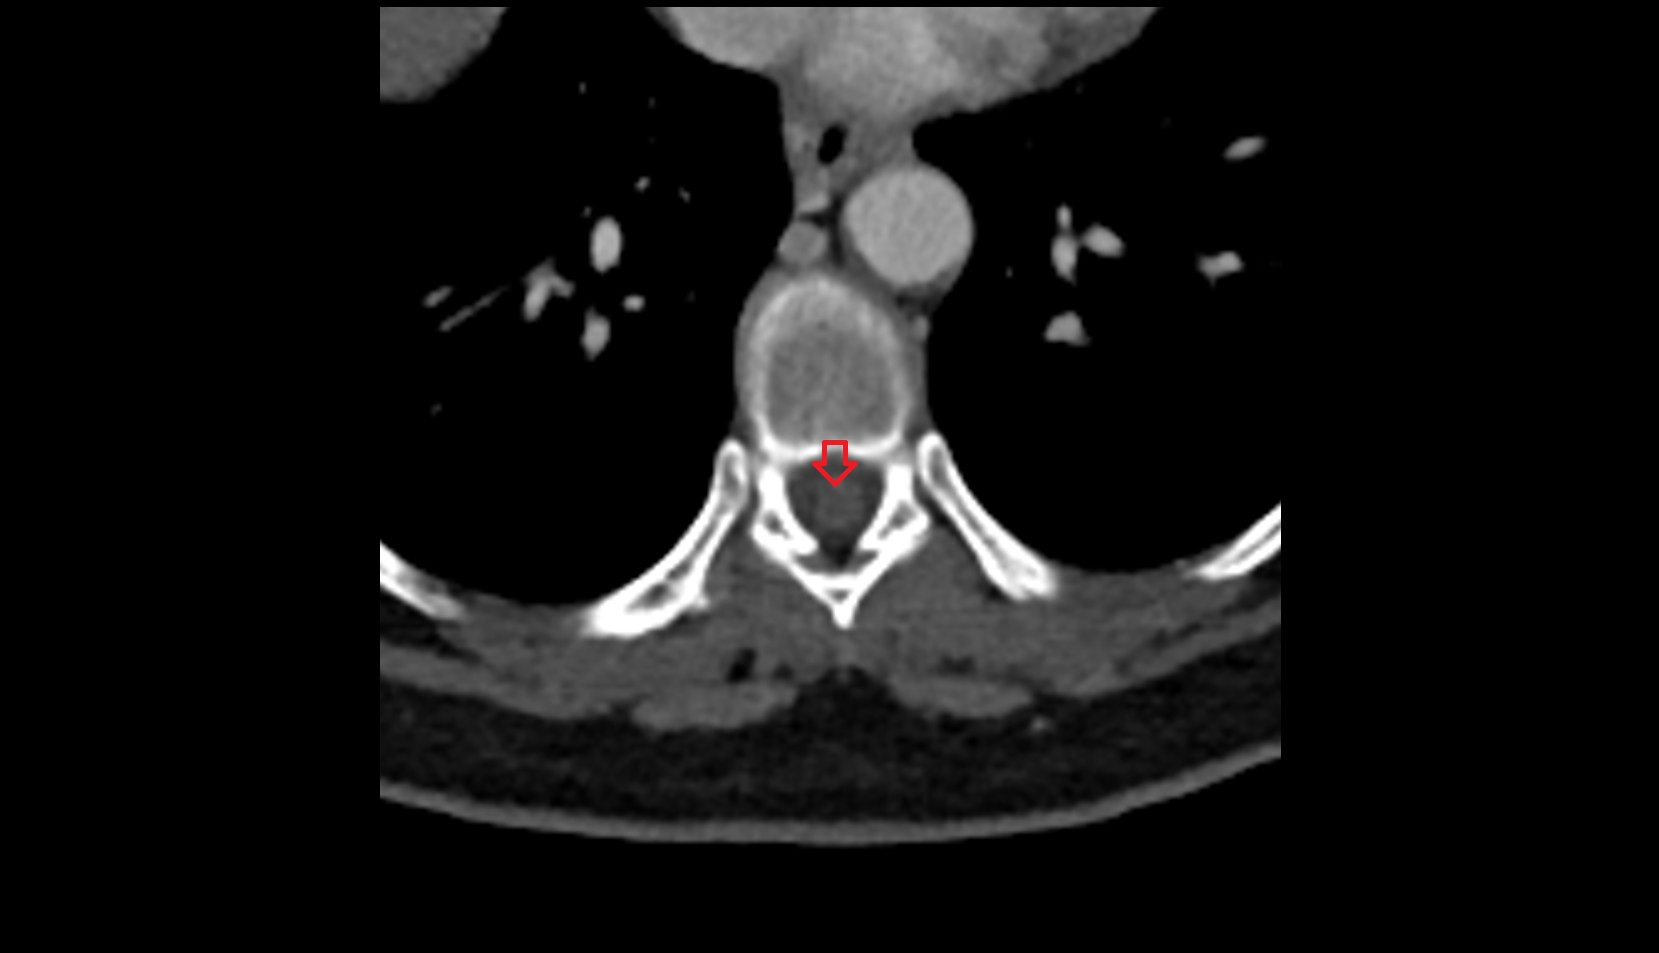

- Spinal cord